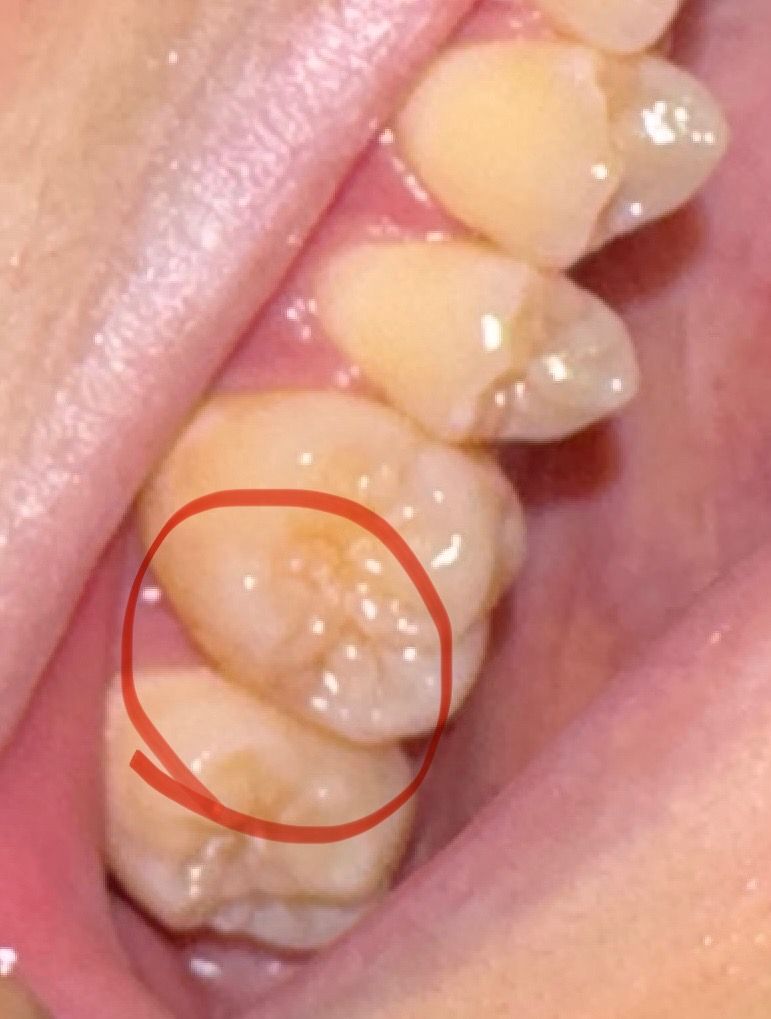

사진 속 치아가 충치인가요??????

어제부터 음식 먹는데 아픈 것도 아니고 간지러운 것도 아니고 뭔가 오묘하게 불편한 느낌이 들더군요

아주 미세한데 제가 예민해서 알아차렸어요

요새 많이 피곤하고 잠도 잘 못자서 예민해져 쓸데없이 잘 느끼는 건지 아니면 그냥 충치인지 모르겠네요

현재 일이 많아 치과를 갈 시간을 낼 수가 없는데 의사선생님들께서 보시기엔 충치라고 생각하시나요?

그리고 치과를 못 가는 상황인데 호전되거나 더 심해지지 않게하는 법 있나요?

사진 상으로 충치가 보이지는 않습니다. 일시적으로 불편한 경우라면 자극만 안주시면 됩니다.

사진상으로는 충치가아닌거 같습니다. 치과에 가셔서 엑스레이를 찍고 검진을 받아보세요.

옆면 충치 가능성 있긴 한데 엑스레이를 찍어봐야 합니다

충치는 알아서 회복되게 할 순 없습니다